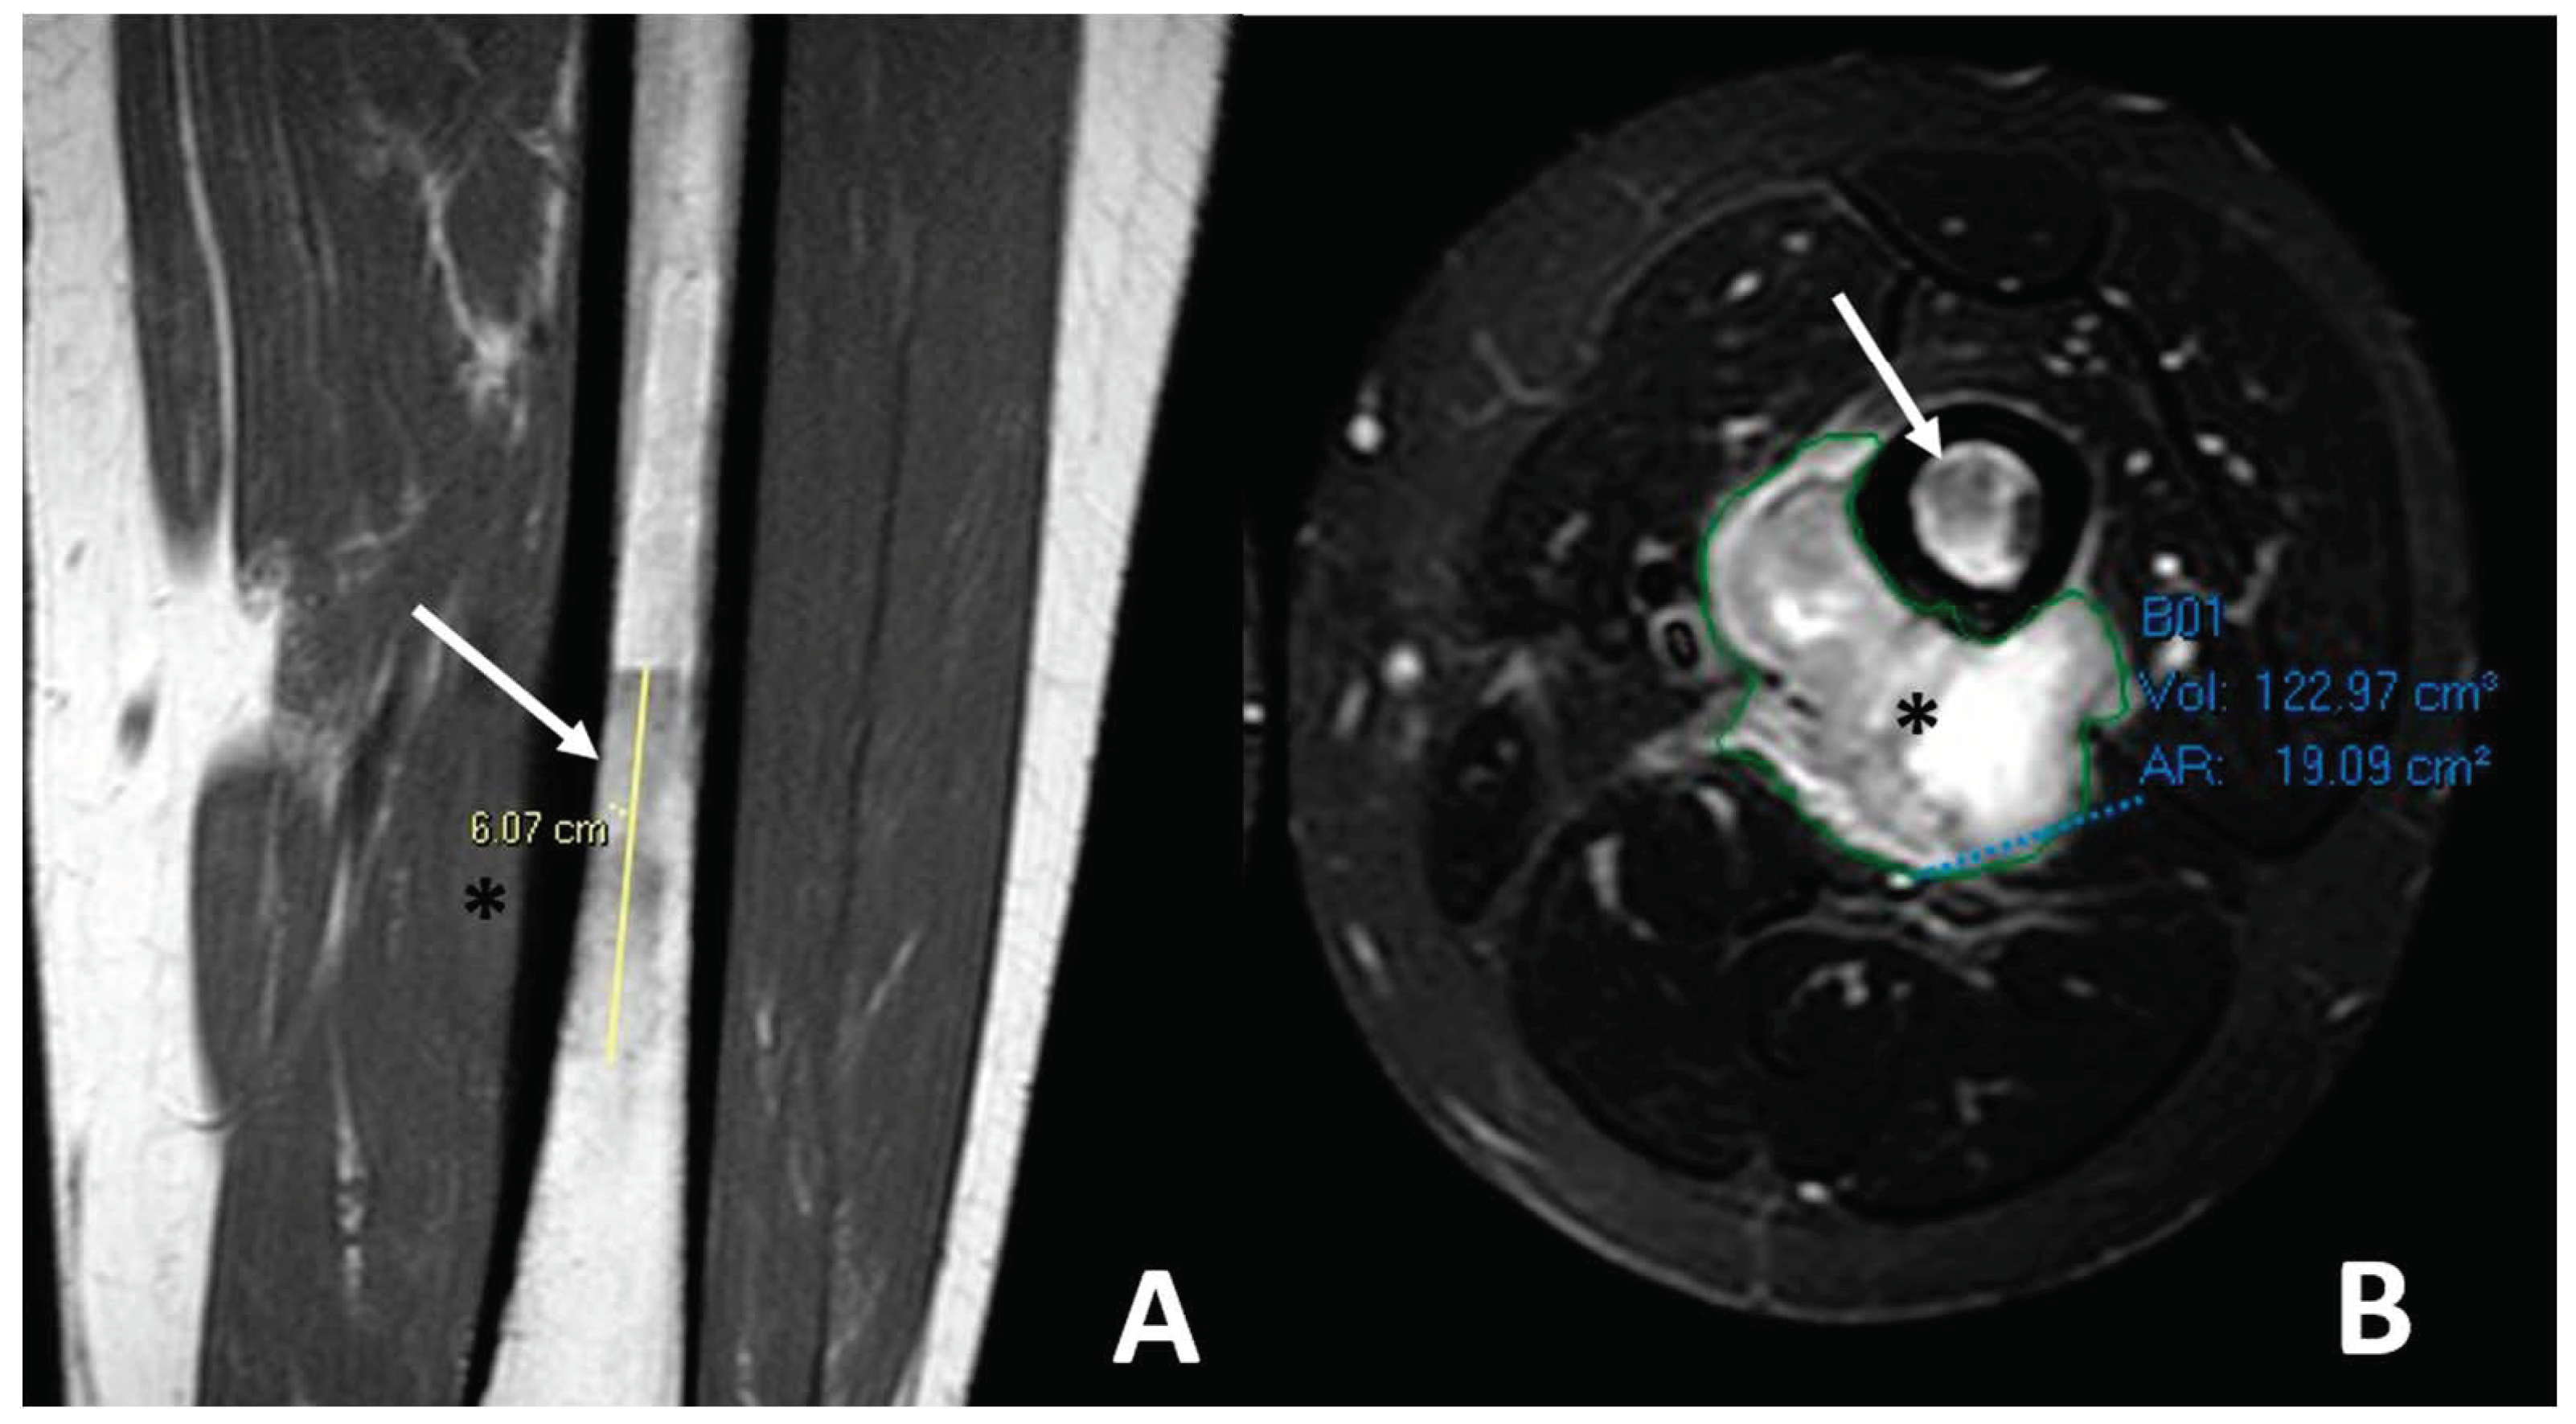

| Telangiectatic | Purely osteolytic | None or thin regular | Multicystic pattern with fluid–fluid levels and solid components on MRI |